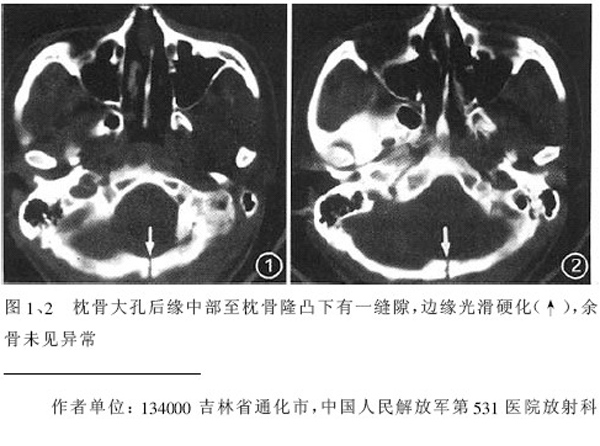

ct 扫描发现枕骨变异一例

温毅,张瑞萍,张延林,尹涛

患者男,19 岁。因头部外伤就诊。体检:营养、发育良好,五官对称,外观无畸形。右额部见局部皮肤青紫,无皮肤破损。ct 扫描:脑组织及颅外软组织未见异常;骨窗见枕骨中下部,由枕骨内、外隆凸至枕骨大孔处有一线样长约27 mm裂隙(图1、2),宽约1 .0 mm。边缘光滑、硬化,贯穿枕骨内外板。颅骨无

凹陷及移位征象。

讨论: 胚胎学研究证实,枕骨发源于脊椎而不是颅骨,在胚胎形成40 ~ 42 体节时,前部5 个体节形成

枕骨。枕骨基底部和鳞部各有一个骨化中心,还有两个枕骨外侧部[1],分别出现于胚胎的第7 周及第8 周。本例枕骨枕鳞部骨缝可能与枕骨各骨化中心发育障碍有关。经枕骨隆凸至枕大孔处骨缝变异极为罕见,易误诊为骨折,细致观察骨缝边缘是否有硬化和软组织是否肿胀即可与骨折相鉴别。